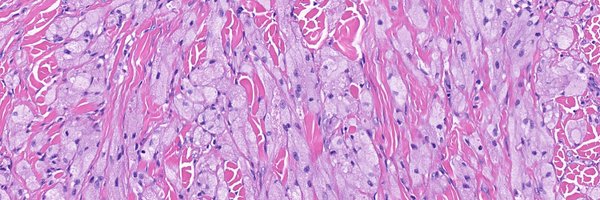

What are these structures called in a nevus? What other tumor has similar structures? Answer (in comments): https://t.co/fRfFXKdTNk More posts from Dr. Moesch @moesch_john: https://t.co/PDDJDJQ9zI

#medTwitter #pathology #pathTwitter #dermpath #dermatology #dermtwitter